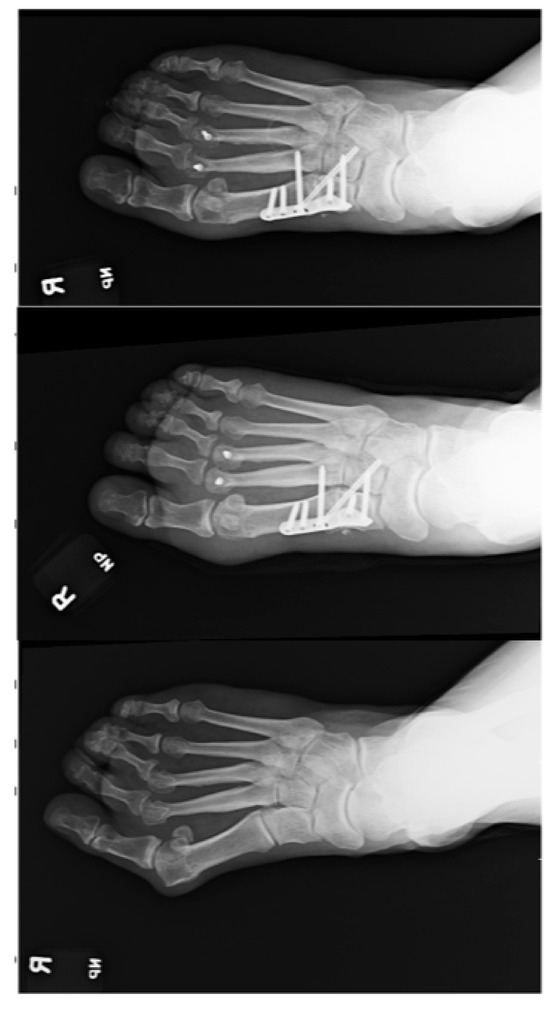

Outcomes of Lapidus Procedure Without Focused Frontal Plane Rotation of the First Metatarsal

J. Am. Podiatr. Med. Assoc. 2026, 116(3), 22; https://doi.org/10.3390/japma116030022 - 23 Apr 2026

Background: We present a retrospective radiographic analysis showcasing the ability to correct hallux valgus using the Lapidus arthrodesis without focused frontal plane rotation of the first metatarsal. Methods: A total of 33 feet in 30 patients who had undergone Lapidus arthrodesis

Background: We present a retrospective radiographic analysis showcasing the ability to correct hallux valgus using the Lapidus arthrodesis without focused frontal plane rotation of the first metatarsal. Methods: A total of 33 feet in 30 patients who had undergone Lapidus arthrodesis for the treatment of hallux abducto valgus deformity from 1 August 2015 to 31 December 2020 were identified. The median age of the cohort was 55.4 years (range, 33–78 years), 23 were female (76.7%), three (10%) underwent bilateral Lapidus arthrodesis, and the median duration of follow-up was 15.9 months (range, 5–72 months). Results: The median (minimum, maximum) preoperative first intermetatarsal angle was 16° (13°, 28°), and at final follow-up it was 5° (0°, 6°) (p < 0.001). The median (minimum, maximum) preoperative hallux abductus angle was 37° (26°, 51°), and at final follow-up it was 8.5° (0°, 22.5°) (p < 0.001). The median (minimum, maximum) preoperative tibial sesamoid position was 6 (4, 7), and at final follow-up it was 3 (2, 5) (p = 0.001). Conclusions: We found the radiographic first metatarsal lateral round sign to be ambiguous. Qualitative comparison of the results of this investigation with prior studies describing outcomes following Lapidus arthrodesis with focused frontal plane rotation of the first metatarsal suggests that similar outcomes can be achieved without employment of a decisive frontal plane rotation of the first metatarsal. Our findings lead us to believe that correction of substantial hallux abducto valgus deformities can be accomplished using the Lapidus procedure combined with lateral release of the first metatarsophalangeal joint without focused derotation of the first metatarsal.